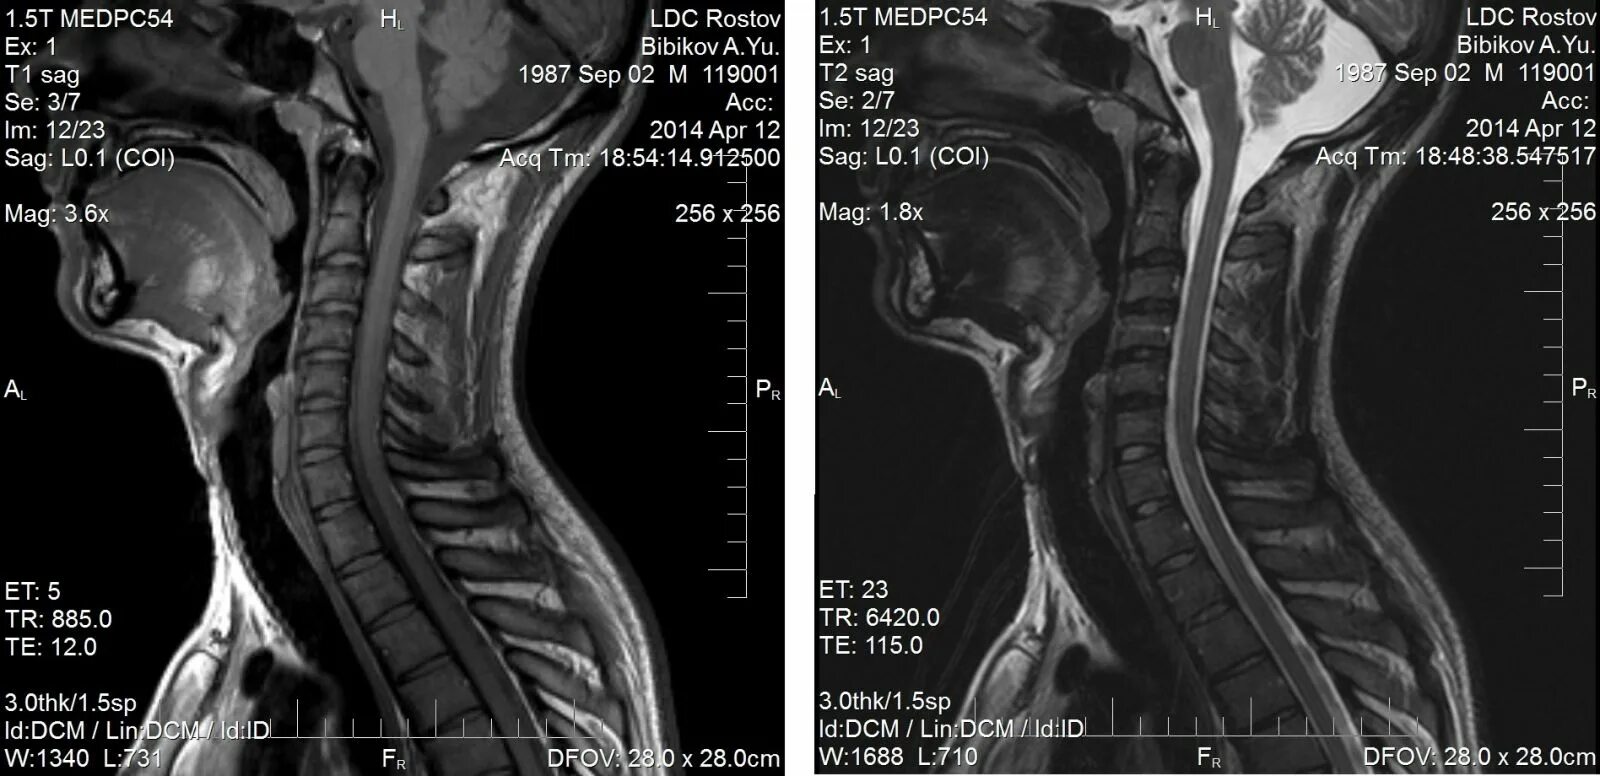

Сколько по времени делается мрт шейного отдела